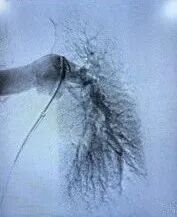

常规消毒、铺巾,2%利多卡因局麻后穿刺右股静脉成功,置入6F鞘管,注入3000u肝素,沿6F鞘管行下腔静脉造影示:右髂静脉-下腔静脉行程血流通畅,未见血栓;交换泥鳅至肺动脉主干,送入猪尾巴管行左右肺动脉造影示:右肺动脉、右上中下肺动脉及分支内可见多发充盈缺损影,相应管腔狭窄;左肺动脉及左上下肺动脉可见充盈缺损影,考虑血栓形成;测得肺动脉压力62/4mmHg。

术前造影